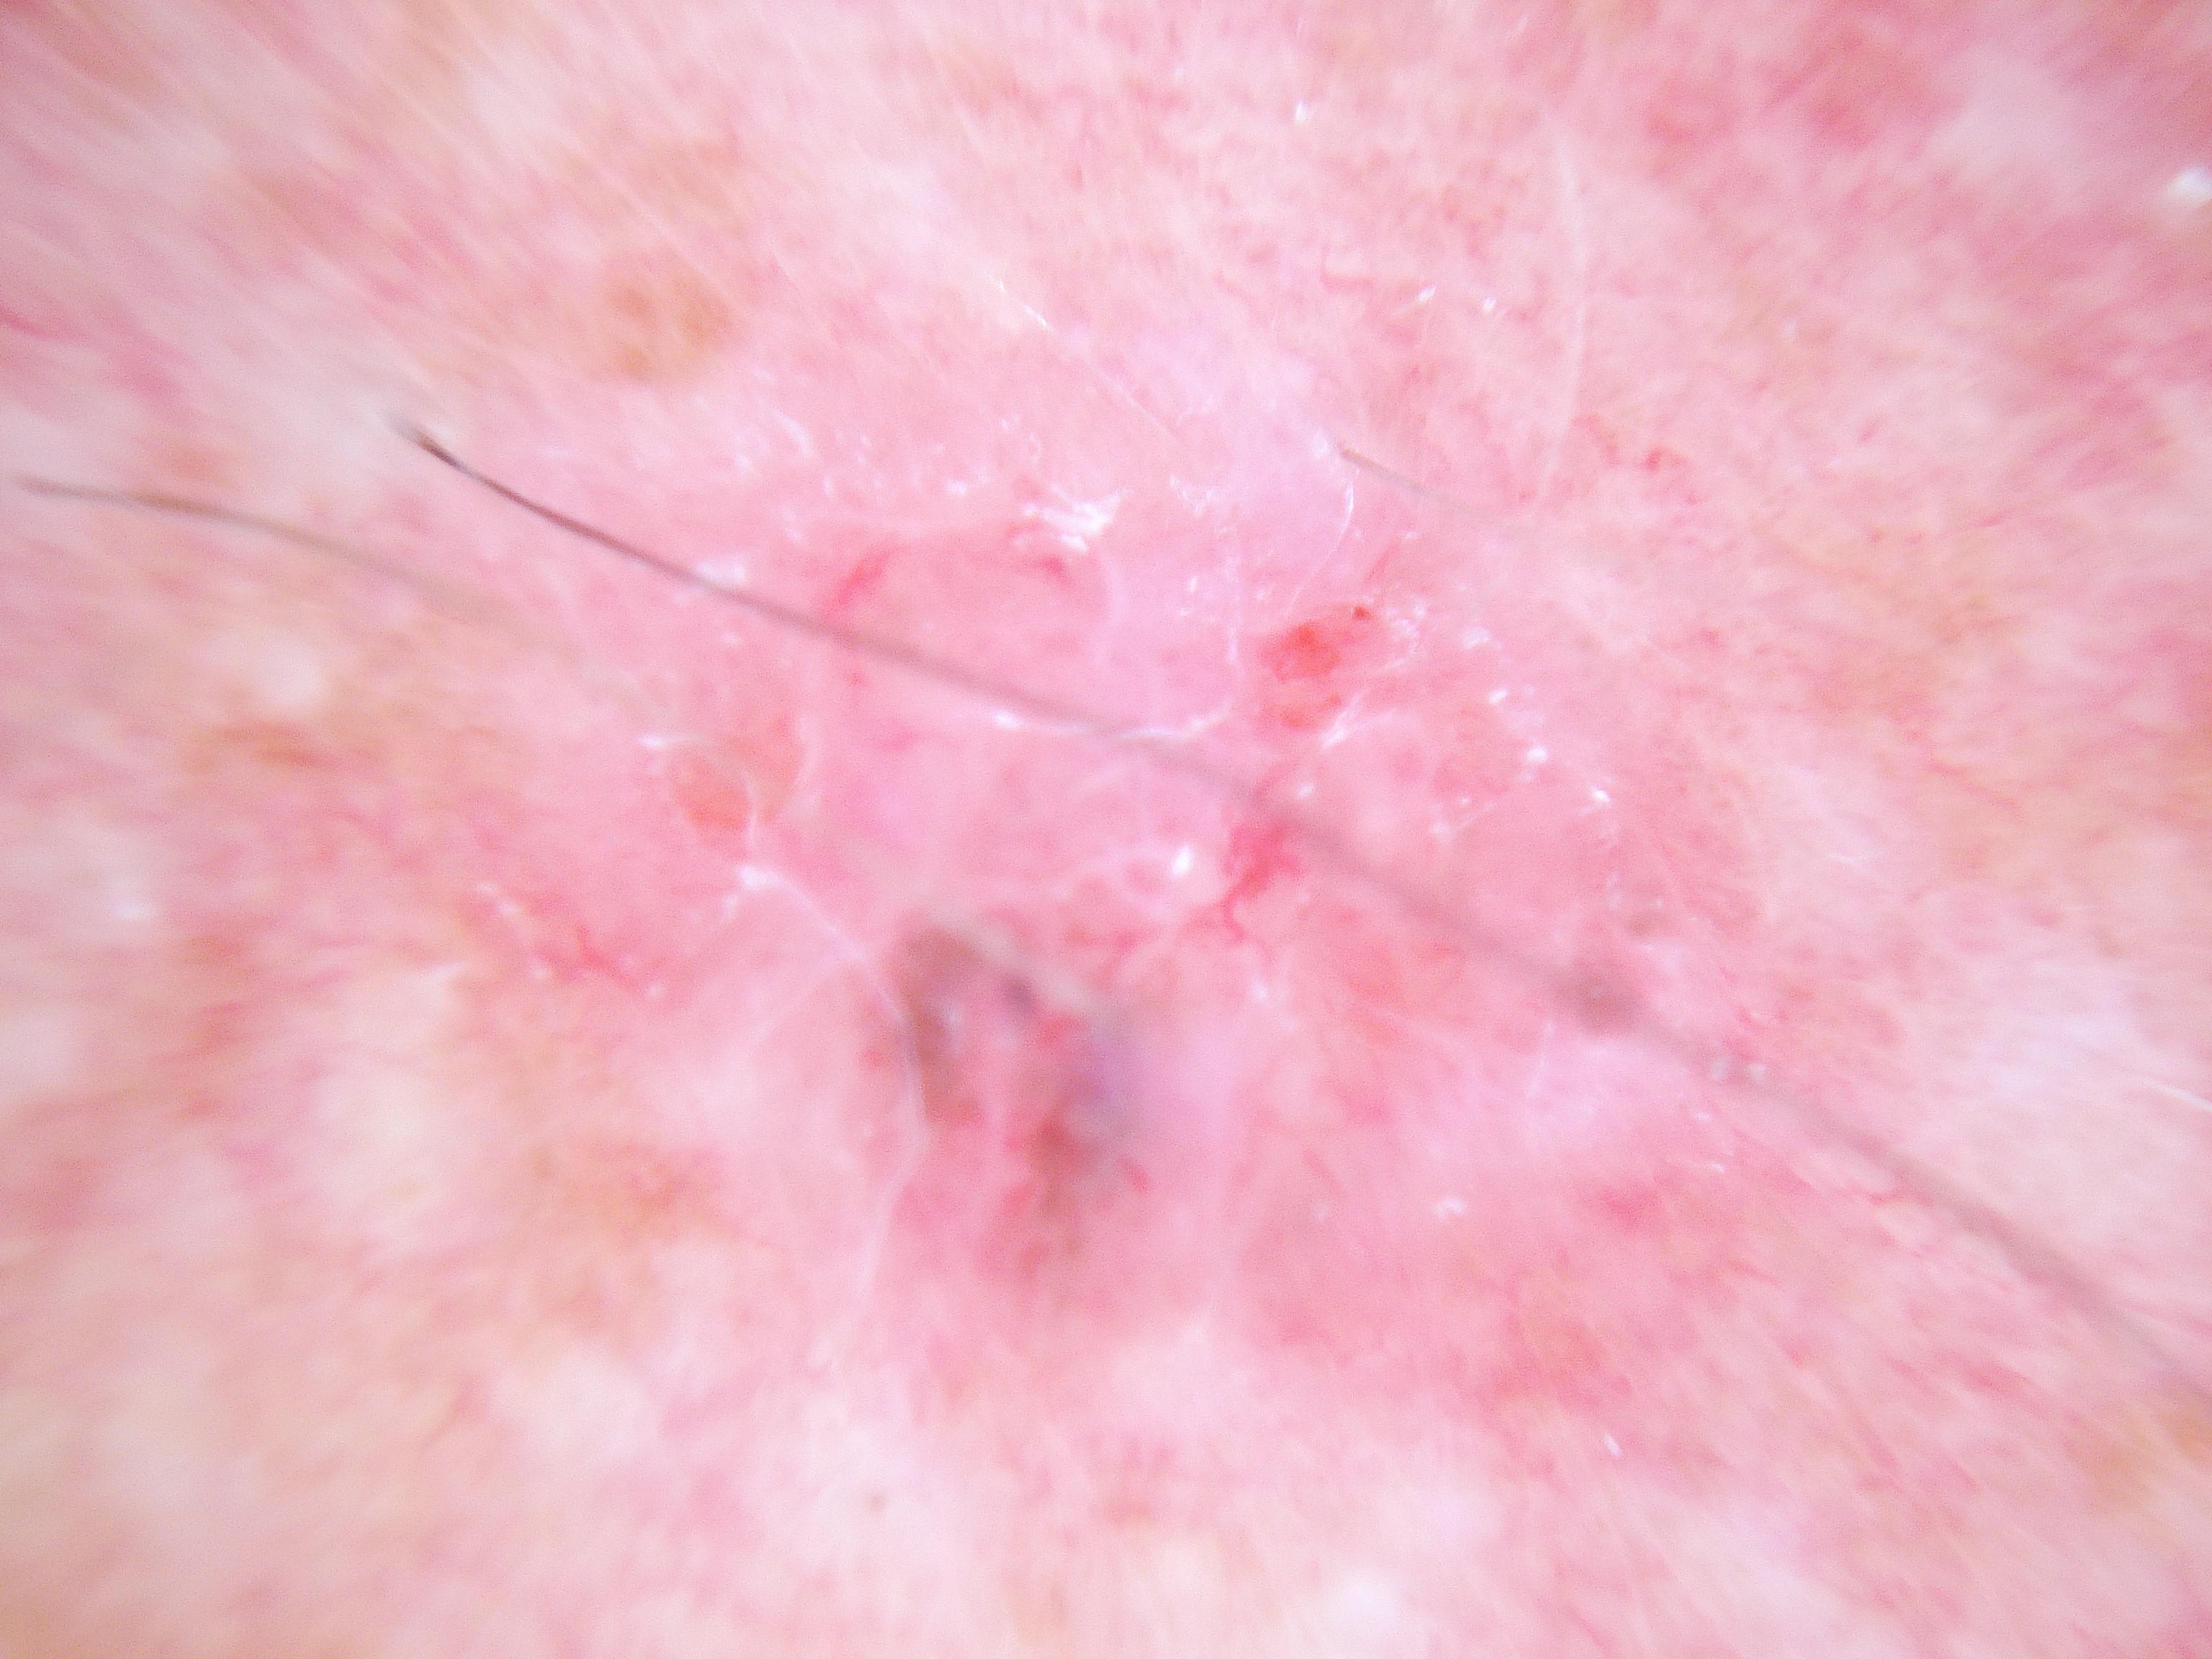

{

"age_approx": 70,

"anatom_site_general": "head/neck",

"concomitant_biopsy": true,

"dermoscopic_type": "contact non-polarized",

"diagnosis_1": "Malignant",

"diagnosis_2": "Malignant melanocytic proliferations (Melanoma)",

"diagnosis_3": "Melanoma in situ",

"diagnosis_confirm_type": "histopathology",

"family_hx_mm": true,

"image_type": "dermoscopic",

"mel_thick_mm": "0.00",

"melanocytic": true,

"patient_id": "IP_9619493",

"personal_hx_mm": true,

"sex": "male"